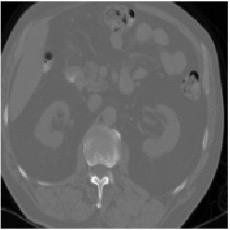

This work presents a novel framework CISFA (Contrastive Image synthesis and Self-supervised Feature Adaptation)that builds on image domain translation and unsupervised feature adaptation for cross-modality biomedical image segmentation. Different from existing works, we use a one-sided generative model and add a weighted patch-wise contrastive loss between sampled patches of the input image and the corresponding synthetic image, which serves as shape constraints. Moreover, we notice that the generated images and input images share similar structural information but are in different modalities. As such, we enforce contrastive losses on the generated images and the input images to train the encoder of a segmentation model to minimize the discrepancy between paired images in the learned embedding space. Compared with existing works that rely on adversarial learning for feature adaptation, such a method enables the encoder to learn domain-independent features in a more explicit way. We extensively evaluate our methods on segmentation tasks containing CT and MRI images for abdominal cavities and whole hearts. Experimental results show that the proposed framework not only outputs synthetic images with less distortion of organ shapes, but also outperforms state-of-the-art domain adaptation methods by a large margin.